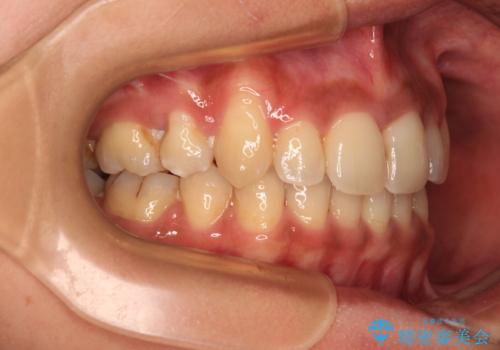

上下の正中位置が大きくずれていたため、上下正中が合わないまま終了することが予想されましたが、思っていた以上にスムーズに歯が移動し、満足いただける仕上がりとなりました。